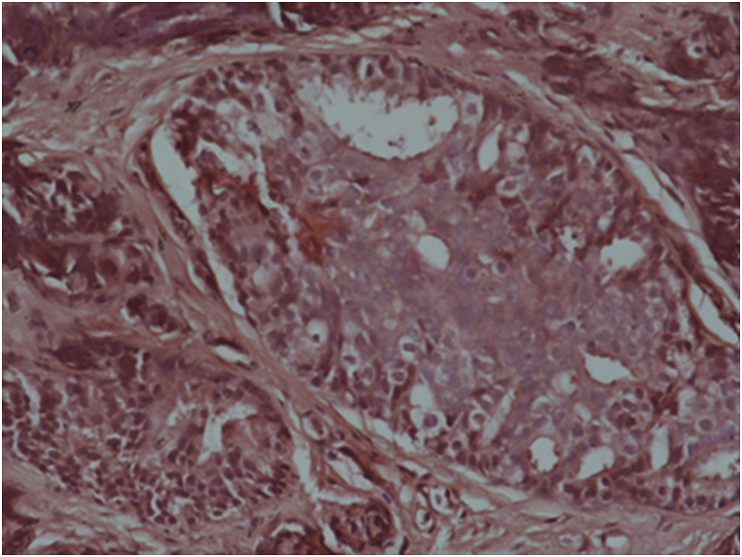

A 65-year-old male with a medical history of heavy smoking (75 pack-year smoking history) was complaining of dysphagia to solids, dysphonia, weight loss and deterioration of the general status since six months. He had a poor performance status (PS = 2). The physical examination revealed a lower gingival lesion (Fig. 1). No cervical lymph nodes were noted. Our patient had weakness and paralysis of the lower limbs. A nasopharyngoscopy was performed. There were no abnormalities during endoscopic examination. A nasopharyngeal biopsy was performed. The histological examination showed a chronic nasopharyngitis. The patient had a gingival biopsy. The anatomopathological examination showed tumor cells proliferation in the lamina propria arranged in small clusters and nests. A cribriform architecture with a stromal fibro-inflammatory reaction were noted. Large cells with atypical nuclei and prominent nucleoli were observed (Fig. 2). Immunohistochemical staining showed that the tumor cells had a diffuse positivity for the prostate specific antigen (PSA) (Fig. 3). The diagnosis of moderately differentiated adenocarcinoma of the prostate was confirmed.

Fig. 2.

Prostatic adenocarcinoma infiltrating gingival mucosa HEX40.